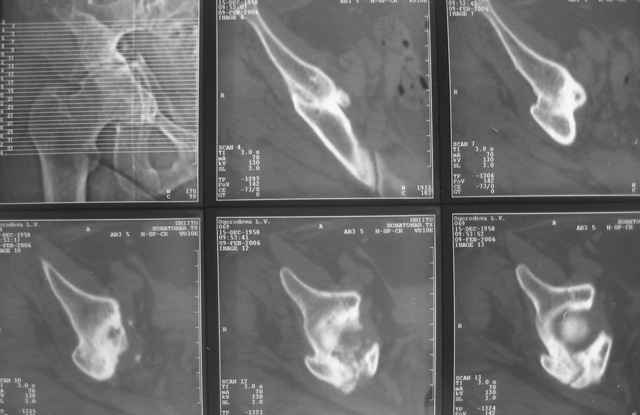

Ув.коллеги, нужен совет по представленному случаю. Пациентка 50лет. В

2003 году в результате дтп получила перелом вертлужной впадины. 1.5

месяца находилась на скелетном вытяжении, в дальнейшем до 10 месяцев

после травмы ходила без опоры на конечность. Вернулась к труду, но в

2006 году перешла на инвалидность и была поставлена в областную

очередь эндопротезирования. В данный момент уже находится в

отделении, но, судя по рентгенограммам и данным КТ, сращения на

уровне перелома не произошло. Что предпочесть?

Имя     : кт-1.jpg

Тип     : image/jpeg

Размер  : 28280 байтов

Описание: отсутствует

Url     : http://weborto.net:8080/pipermail/ortho/attachments/20090324/8863a2fd/attachment-0007.jpg